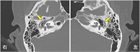

1. 多発血管炎性肉芽腫症(granulomatosis with polyangiitisGPA患者ではANCA(anti-neutrophil cytoplasmic antibodies)の陽性率は高い。腎症を伴う全身型の場合は80~90%で陽性である。また、頭頚部または肺のみに病変を認める限局型の場合は約60%で陽性である。したがって、GPAを疑う患者でのPR3-ANCA(c-ANCA)、MPO-ANCA(p-ANCA)測定は推奨される(推奨度1)